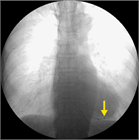

1. 急性心筋梗塞(特に下壁梗塞)に合併する房室ブロックには、一時ペーシングを挿入して管理することが勧められる(推奨度1)

1. 一時ペーシングは、緊急臨床現場だけでなく潜在的な伝導障害を有する場合や、高度房室ブロックなどへの移行、進行の可能性がある場合にも使用されることがある。例)現時点で循環動態を維持できている徐脈患者が全身麻酔下での手術を受ける場合、ペースメーカ感染等でペースメーカシステムの全抜去が必要となった場合など